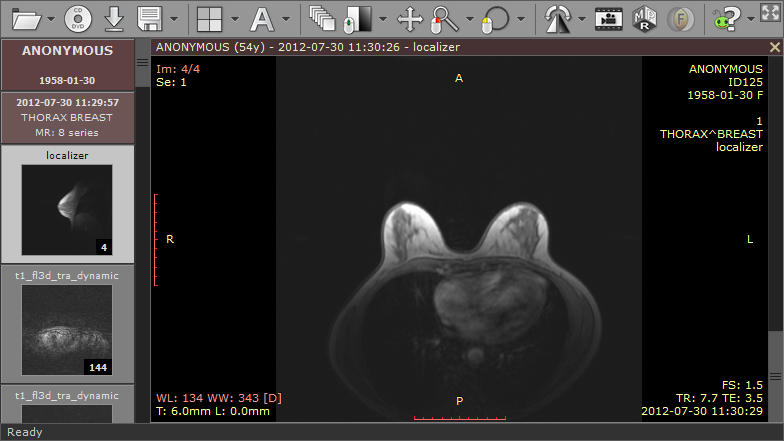

1) 打开含有动态序列的检查。

2) 按 F4 打开「打开多序列」窗口,选择动态序列(包括未增强序列)。启用了减影功能的序列也很有用,可快速定位病变。

3) 找到要分析的病变,在其上方绘制椭圆 ROI。